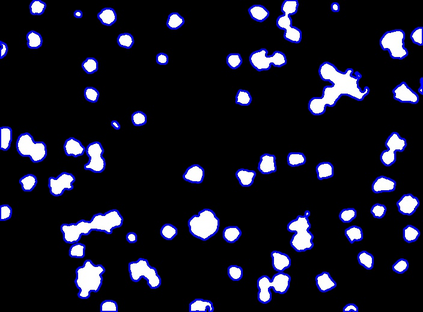

Bright-field microscopy, a cost-effective solution for live-cell culture, is often the only resource available, along with standard CPUs, for many low-budget labs. The inherent challenges of bright-field images -- their noisiness, low contrast, and dynamic morphology -- coupled with a lack of GPU resources and complex software interfaces, hinder the desired research output. This article presents a novel microscopy image analysis framework designed for low-budget labs equipped with a standard CPU desktop. The Python-based program enables cytometric analysis of live, unstained cells in culture through an advanced computer vision and machine learning pipeline. Crucially, the framework operates on label-free data, requiring no manually annotated training data or training phase. It is accessible via a user-friendly, cross-platform GUI that requires no programming skills, while also providing a scripting interface for programmatic control and integration by developers. The end-to-end workflow performs semantic and instance segmentation, feature extraction, analysis, evaluation, and automated report generation. Its modular architecture supports easy maintenance and flexible integration while supporting both single-image and batch processing. Validated on several unstained cell types from the public dataset of livecells, the framework demonstrates superior accuracy and reproducibility compared to contemporary tools like Cellpose and StarDist. Its competitive segmentation speed on a CPU-based platform highlights its significant potential for basic research and clinical applications -- particularly in cell transplantation for personalised medicine and muscle regeneration therapies. The access to the application is available for reproducibility